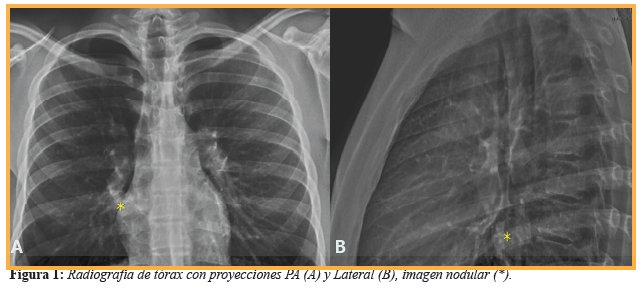

Al cabo de 4 semanas, en el seguimiento clínico-radiológico, los padres refieren accesos de tos a predominio nocturno que cede con el broncodilatador, pero se observó una imagen nodular en proyección del cuerno inferior del hilio derecho que medía 23x25x25 mm en sus diámetros (anteroposterior, transversal, longitudinal), la cual no se visualizaba debido al proceso de condensación en la fase neumónica (Figura 1). Se decidió realizar Tomografía Computarizada (TC) de tórax a nivel de T-7 Ventana de pulmón (A) para su caracterización la que constató que hacia la luz del bronquio para el lóbulo inferior derecho crecía una lesión nodular tumoral de 29x24x25 mm (Anteroposterior, Transversal, longitudinal) con densidad de 40 UH (Unidades Hounsfield) la cual oblitera parcialmente la luz del bronquio en el estudio simple (Figura 2) y 90-116 UH en el estudio contrastado (C) mostrando lesión nodular que capta intensamente el contraste (Figura 2). En el postprocesamiento, se obtuvo broncoscopía virtual la cual validó la presencia de una lesión endoluminal nacarada que obstruye parcialmente la luz del bronquio para el lóbulo inferior derecho (Figura 3) adyacente a la misma, se observa la emergencia del bronquio para el lóbulo medio.